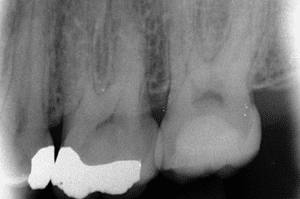

Fig 7

Radiographie rétro-alvéolaire après finition de la restauration d’usage.